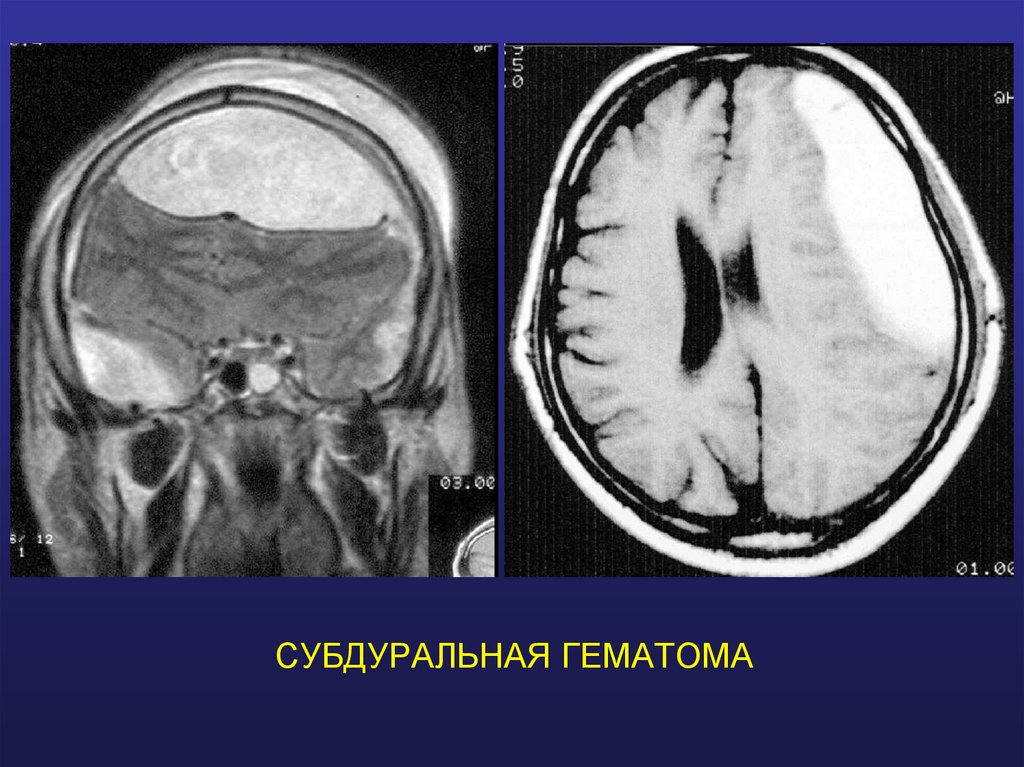

СУБДУРАЛЬНАЯ ГЕМАТОМА

23. СУБДУРАЛЬНАЯ ГЕМАТОМА

МОРФОЛОГИЧЕСКАЯ КЛАССИФИКАЦИЯ

Гематомы

• Эпидуральная

• Субдуральная

• Внутримозговая